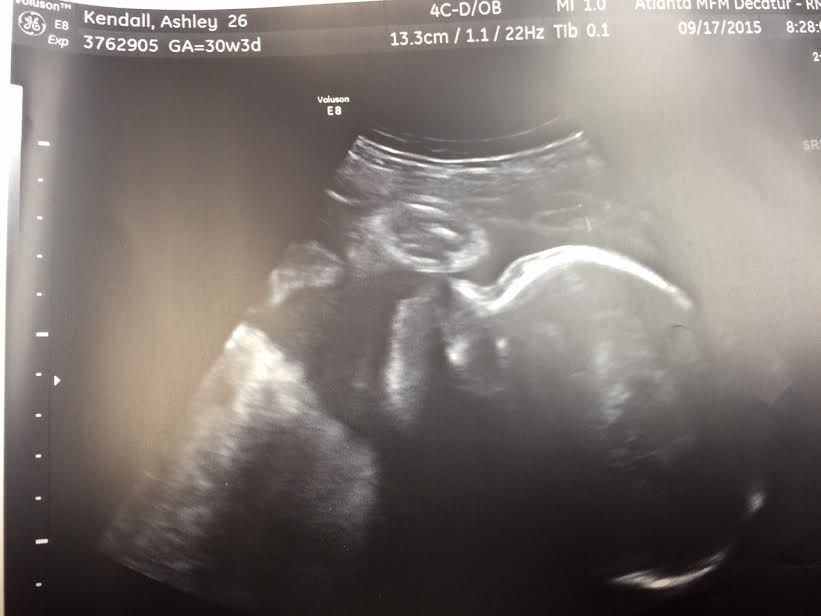

Worked with Dad on birthing hypnosis. P is going to be here next week. I can feel it.